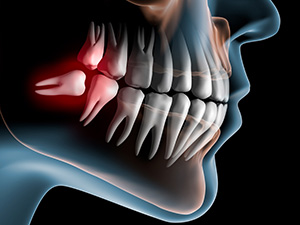

一般的に17~30歳頃に生えてくる前歯から数えて8番目の歯のことをいいます。永久歯の中で一番最後に生えてくるためスペースがなく、横や斜めに傾いたり、骨の中に埋まったまま生えてこない場合があります。

一般的に17~30歳頃に生えてくる前歯から数えて8番目の歯のことをいいます。永久歯の中で一番最後に生えてくるためスペースがなく、横や斜めに傾いたり、骨の中に埋まったまま生えてこない場合があります。